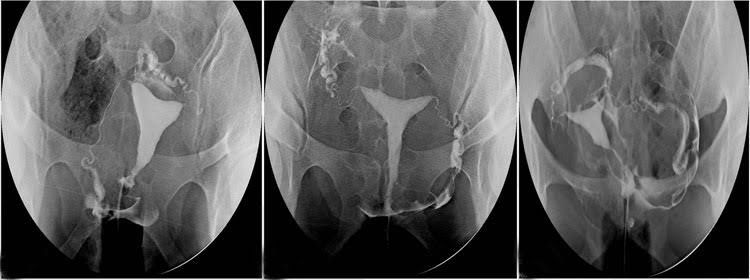

İnfertilite (kısırlık) değerlendirmesinde istenen temel testlerden birisidir. Ayrıca rahim ağzına veya rahme uygulanan bir müdahale sonrasında (kürtaj gibi) adet kanamalarının kesilmesi ya da çok azalması durumunda rahim ağzı kanalındaki muhtemel bir tıkanıklığın veya rahim içerisindeki muhtemel bir yapışıklığın (Asherman sendromu) değerlendirilmesinde, tekrarlayan düşüklerde rahimde doğumsal bir gelişim kusuru bulunup bulunmadığının (aşağıda soldaki resim – bölmeli rahim) belirlenmesinde de yaygın olarak kullanılır.

Rahim filmi bir Kadın Hastalıkları ve Doğum Uzmanı ve Radyoloji Uzmanı veya Teknisyeni tarafından beraberce uygulanır. Jinekolojik muayene pozisyonundayken rahim ağzını görüntülemek için vajinaya alet yerleştirilir. Daha sonra rahme kanül adı verilen bir diğer alet yerleştirilir. Kanüle tutturulan enjektörden birkaç aşamada basınç uygulanarak kontrast madde (ilaçlı madde) verilir. Bu sıvı röntgen filminde bulunduğu yerlerde ışını geçirmediğinden beyaz bir görünüm kazandırır. Sıvı verilmesi esnasında ya belli aralıklarla röntgen filmleri alınır veya floroskopi adı verilen yöntem kullanılarak ekrandan sıvının geçişi sürekli olarak izlenir ve kaydedilir. Böylelikle rahmin içyapısı, kanalların açık olup olmadığı ve yapıları değerlendirilir. HSG, röntgen ışınları yardımıyla gerçekleştirilen bir teknik olmasına karşın verilen ışın dozu yüksek değildir.